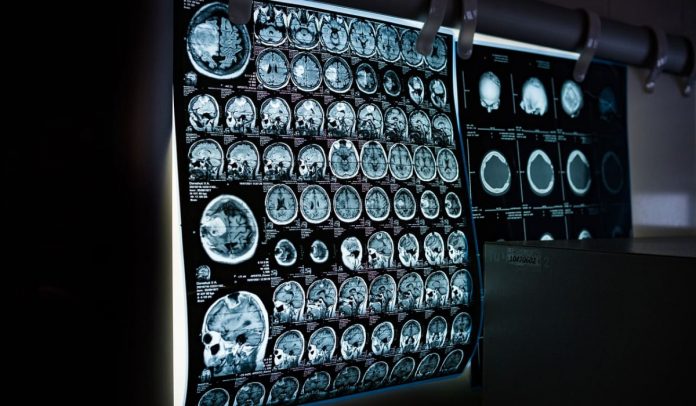

Subcortical small vessel disease leads to lacunar infarcts and progressive damage to the white matter.

The study confirms that a biomarker for vascular injury, based on the ratio of the protein albumin in spinal fluid and blood, was significantly higher in patients with subcortical small-vessel disease. The study also presents a new biomarker, a fragment of the amyloid precursor protein (APP) in spinal fluid, which was lower in patients with subcortical small-vessel disease.

- In contrast, subcortical small-vascular disease affects vessels deep within the brain, below the cerebral cortex, so that the cognitive symptoms are different. Patients often suffer sudden personality changes and slowed mental acuity before memory becomes noticeably diminished.